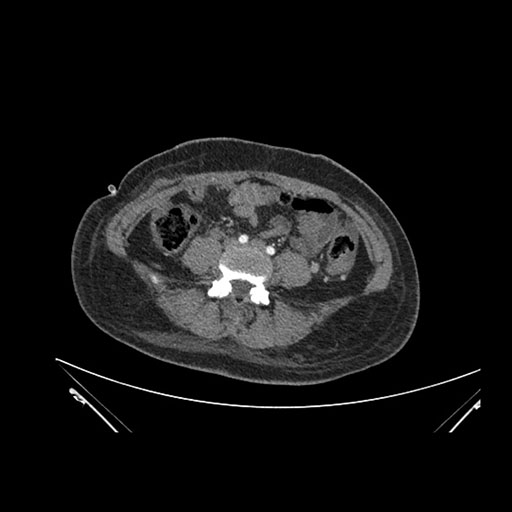

Imaging Analysis

Look through the patient's CT scan to identify any areas of concern for the necessary procedure.

Axial Venous

Based on initial findings, which issue(s) would you be most concerned about?